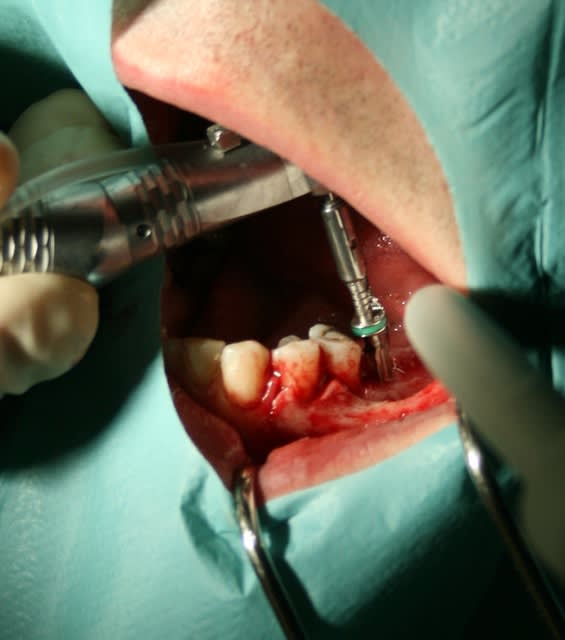

Mise en place de 2 implants IDI Idcam , très bonne impression , forage hypersimplifié ( 4 forets pour du 5.2),et sécurisé grâce aux forets à butée, excellente sensations lors de la mise en place à la clef à cliquet à la position souhaité / à l'os crestal.

Juste un regret la préhension de l'implant se fait de manière manuel avec un porte implant en plastique un poil trop large qui peut s'avérer délicat d'utilisation entre 2 dents étroites et qui contre indique l'usage abusif de café...